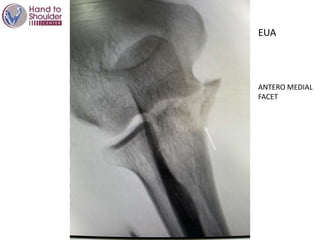

EUA

ANTERO MEDIAL

FACET